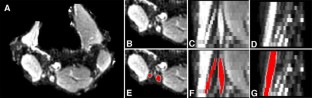

Clinical trial design in amyotrophic lateral sclerosis (ALS) remains hampered by a lack of reliable and sensitive biomarkers of disease progression. The present study evaluated peripheral nerve diffusion tensor imaging (DTI) as a surrogate marker of axonal degeneration in ALS. Longitudinal studies were undertaken in 21 ALS patients studied at 0 and 3 months, and 19 patients at 0, 3 and 6 months, with results compared to 13 age-matched controls. Imaging metrics were correlated across a range of functional assessments including amyotrophic lateral sclerosis functional rating scale revised (ALSFRS-R), lower limb muscle strength (Medical Research Council sum score, MRCSS-LL), compound muscle action potential amplitudes and motor unit number estimation (MUNE). Fractional anisotropy was reduced at baseline in ALS patients in the tibial (p < 0.05), and peroneal nerve (p < 0.05). Fractional anisotropy and axial diffusivity declined in the tibial nerve between baselines, 3- and 6-month scans (p < 0.01). From a functional perspective, ALSFRS-R correlated with fractional anisotropy values from tibial (R = 0.75, p < 0.001) and peroneal nerves (R = 0.52, p = 0.001). Similarly, peroneal nerve MUNE values correlated with fractional anisotropy values from the tibial (R = 0.48, p = 0.002) and peroneal nerve (R = 0.39, p = 0.01). There were correlations between the change in ALSFRS-R and tibial nerve axial diffusivity (R = 0.38, p = 0.02) and the change in MRCSS-LL and peroneal nerve fractional anisotropy (R = 0.44, p = 0.009). In conclusion, this study has demonstrated that some peripheral nerve DTI metrics are sensitive to axonal degeneration in ALS. Further, that DTI metrics correlated with measures of functional disability, strength and neurophysiological measures of lower motor neuron loss.